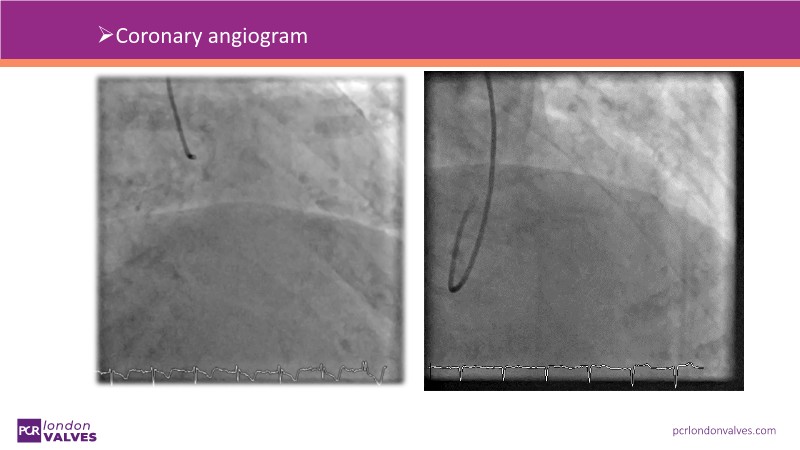

This session addresses emerging topics in structural heart disease by examining patient-centered solutions such as EVOQUE transcatheter tricuspid valve replacement (TTVR) and SAPIEN transcatheter heart valve-in-heart valve (THV-in-THV) procedures. It covers the latest data from Europe on redo TAVI, lifetime management strategies beginning with initial prosthesis planning, evolving patient selection for TTVR, and features an educational live case alongside expert panel discussions on procedure safety and efficacy.

- To understand the latest considerations and techniques for redo TAVI and get exposed to the latest data from Europe

- To learn how to maximise the benefits of TAVI with a lifetime management strategy that starts with the planning of the first prosthesis